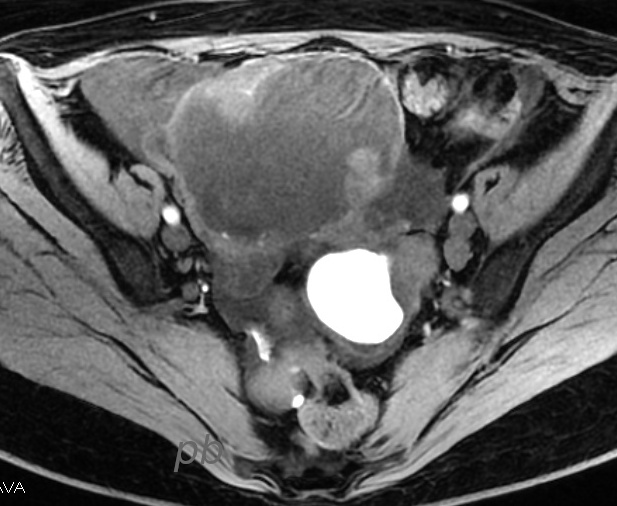

IRM axial T1 fatsat

Kyste endométriosique sur chaque ovaire (★) en hypersignal T1, contenant de petites images végétantes (►). Pas de prise de contraste après injection.

La patiente est opérée peu après : endométriose stade 4. Kystectomie ovarienne droite.

Diagnostic de kyste endométriosique confirmé en anapath.